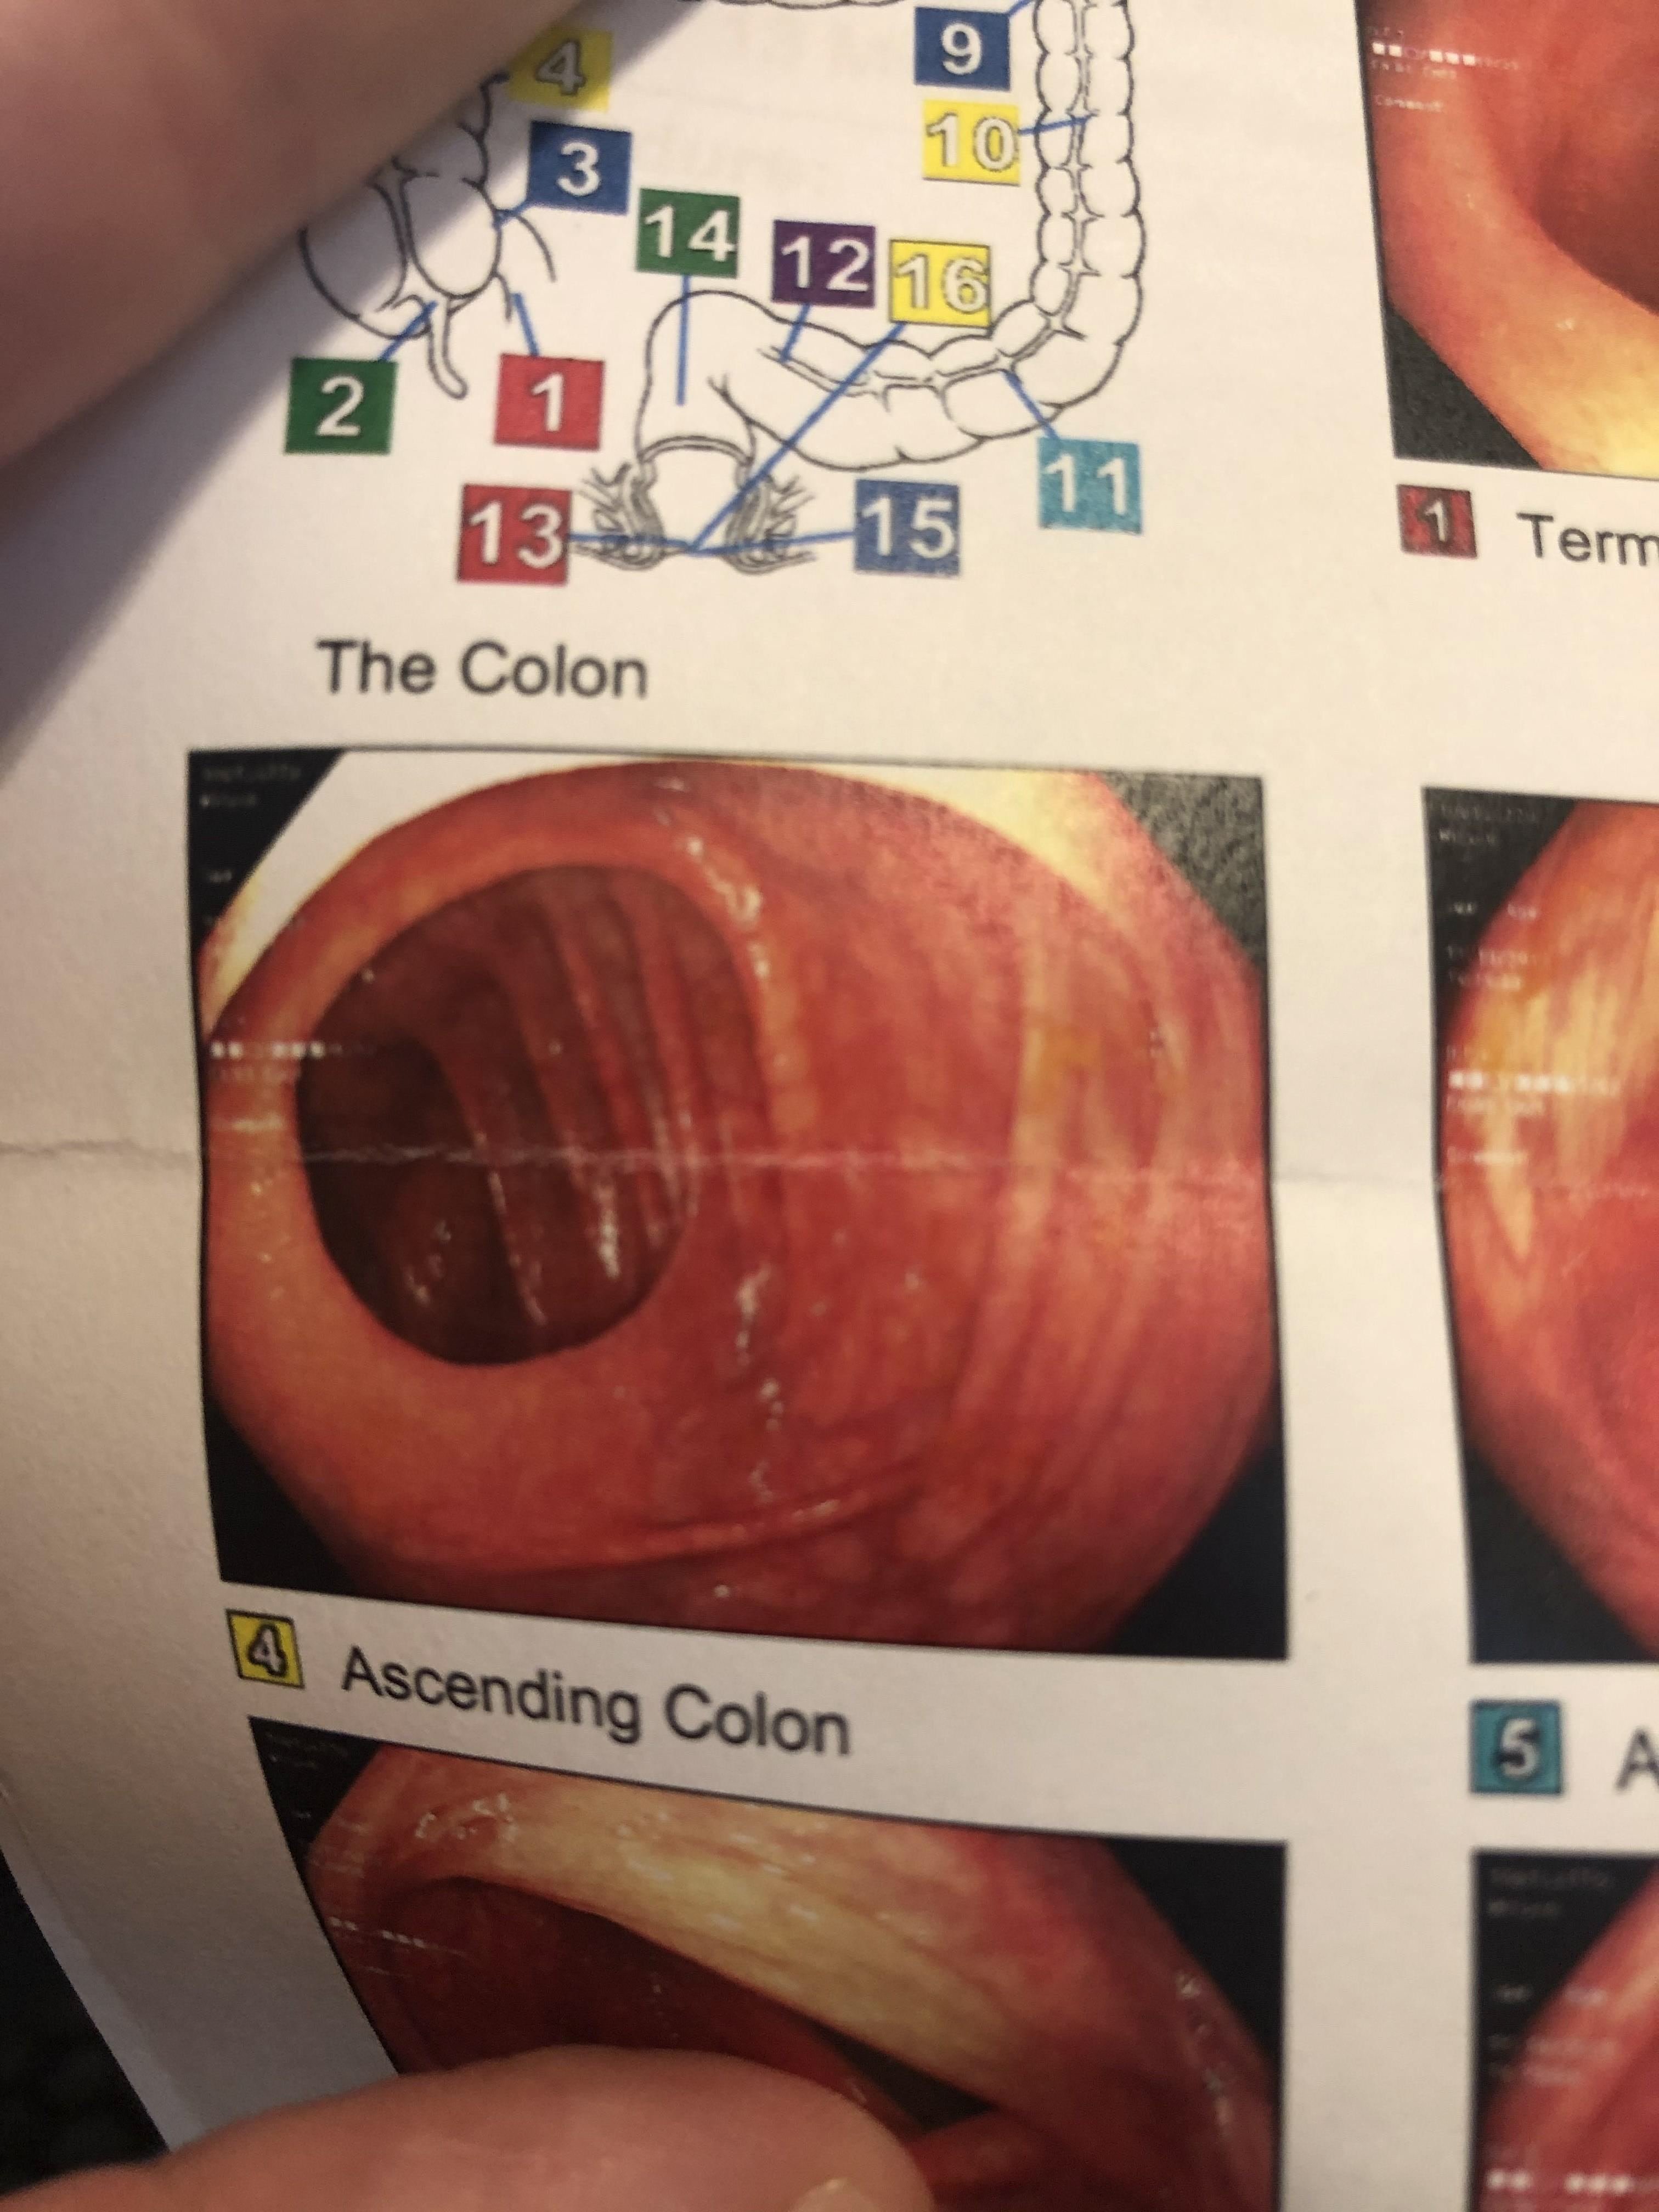

I developed a horrible anal fissure prior to my departure to Japan that made my experience in Naoshima indescribably painful. The goal of this study was to filter the experience of my anal fissure, realized as photos from a subsequent colonoscopy, through the parallel experience of Tadao Ando's structure.

Next, I created a simple collage of photos from my colonoscopy based on Chichu's topology.